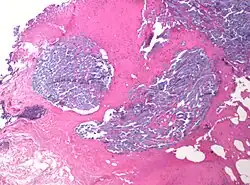

Desmoplasia is usually only associated with malignant neoplasms, which can evoke a fibrotic response invading healthy tissue. Invasive ductal carcinomas of the breast often have a stellate appearance caused by desmoplastic formations.

Desmoplasia refers to growth of dense connective tissue or stroma.[2] This growth is characterized by low cellularity with hyalinized or sclerotic stroma and disorganized blood vessel infiltration.[3] This growth is called a desmoplastic response and occurs as result of injury or neoplasia.[2] This response is coupled with malignancy in non-cutaneous neoplasias, and with benign or malignant tumors if associated with cutaneous pathologies.[3]

A desmoplastic response is characterized by larger stromal cells with increased extracellular fibers and immunohistochemically by transformation of fibroblastic-type cells to a myofibroblastic phenotype.[2] Myofibroblastic cells in tumors are differentiated from fibroblasts for their positive staining of smooth-muscle actin (SMA).[2] Furthermore, an increase in total fibrillar collagens, fibronectins, proteoglycans, and tenascin C are distinctive of the desmoplastic stromal response in several forms of cancer.[14] Expression of tenascin C by breast cancer cells has been demonstrated to allow for metastasis to the lungs and cause the expression of tenascin C by the surrounding tumor stromal cells.[15] In addition, tenascin C is found extensively in pancreatic tumor desmoplasia as well.[16]